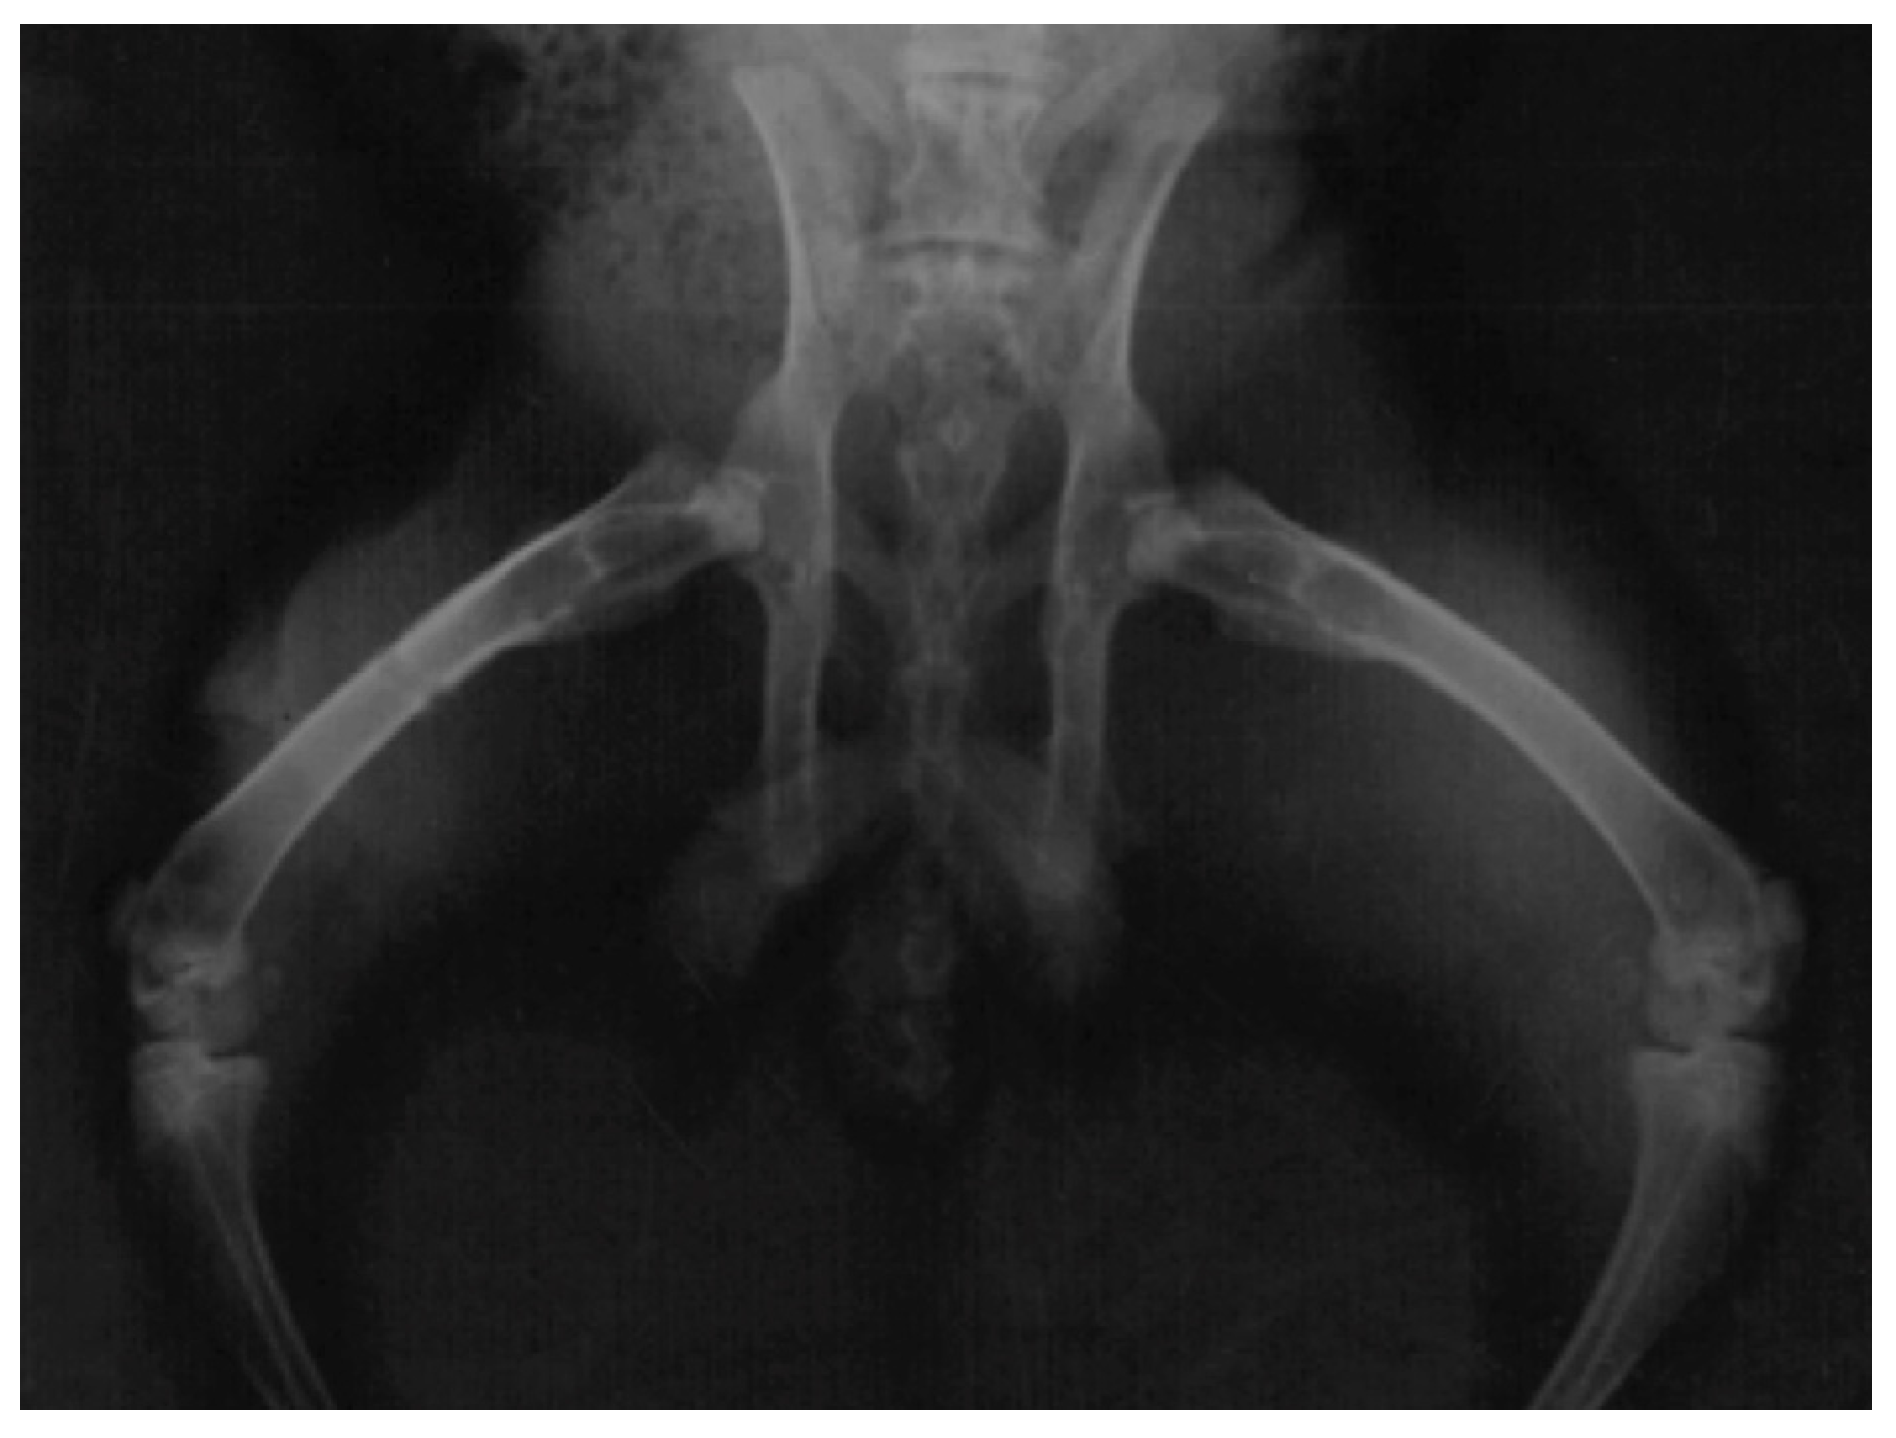

2.7. Radiographic Assessment

3.4. Radiographic Assessment